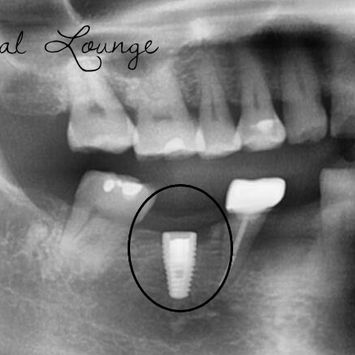

Immediate Implant Replacement with Bone Grafting at #46 Following Failed Implant Removal

CBCT taken showing suitable bone availability; no red flags.

CBCT reviewed: failed implant confirmed, adequate bone morphology for immediate replacement.

Surrounding anatomical structures assessed; IDN trajectory noted.

Post-operative CBCT confirms good implant position and alignment; IDN not involved.